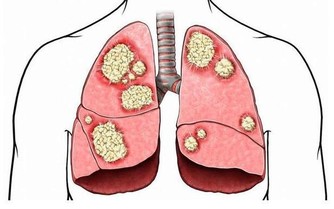

*****4.肺——深呼吸*****

深深地吸一口氣,再緩緩吐出,一次深呼吸就完成了。動作雖然簡單,作用卻不少。

深呼吸能更好地排出肺部的殘餘氣體和其他代謝廢物,有助於保持肺部清潔,保護呼吸道,還能在一定程度上緩解肺部不適。

心肝胃肺腎,各有1個最愛的養生小動作! 照著做,五臟養好疾病不擾

此外,適當的深呼吸還有減輕疲憊、舒緩情緒的作用。

注意:

不建議一次性做太多深呼吸,因為這可能會導致呼吸性鹼中毒;

如果平時經常無意識地深呼吸,並伴有頭暈、眼花、四肢麻木等症狀,可能是疾病的表現,建議及時就醫。